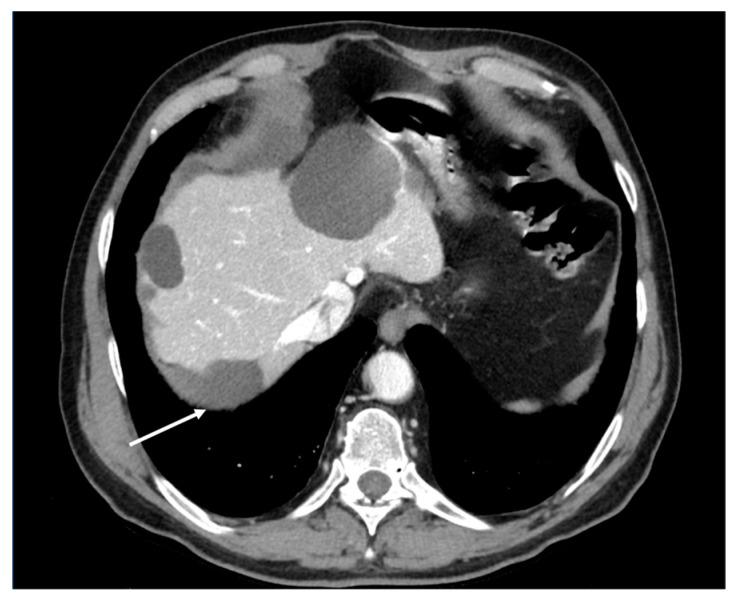

Peritoneal carcinosis is a condition characterized by the spread of cancer cells to the peritoneum, which is the thin membrane that lines the abdominal cavity. It is a serious condition that can result from many different types of cancer, including ovarian, colon, stomach, pancreatic, and appendix cancer. The diagnosis and quantification of lesions in peritoneal carcinosis are critical in the management of patients with the condition, and imaging plays a central role in this process. Radiologists play a vital role in the multidisciplinary management of patients with peritoneal carcinosis. They need to have a thorough understanding of the pathophysiology of the condition, the underlying neoplasms, and the typical imaging findings. In addition, they need to be aware of the differential diagnoses and the advantages and disadvantages of the various imaging methods available. Imaging plays a central role in the diagnosis and quantification of lesions, and radiologists play a critical role in this process. Ultrasound, computed tomography, magnetic resonance, and PET/CT scans are used to diagnose peritoneal carcinosis. Each imaging procedure has advantages and disadvantages, and particular imaging techniques are recommended based on patient conditions. Our aim is to provide knowledge to radiologists regarding appropriate techniques, imaging findings, differential diagnoses, and treatment options. With the advent of AI in oncology, the future of precision medicine appears promising, and the interconnection between structured reporting and AI is likely to improve diagnostic accuracy and treatment outcomes for patients with peritoneal carcinosis.

腹膜癌是一种以癌细胞扩散至腹膜为特征的病症,腹膜是衬于腹腔的一层薄膜。它是一种严重的病症,可由多种不同类型的癌症引发,包括卵巢癌、结肠癌、胃癌、胰腺癌和阑尾癌。腹膜癌中病变的诊断和定量对于该病症患者的管理至关重要,而影像学在这一过程中发挥着核心作用。放射科医生在腹膜癌患者的多学科管理中起着至关重要的作用。他们需要对该病症的病理生理学、潜在肿瘤以及典型的影像学表现有透彻的了解。此外,他们需要知晓鉴别诊断以及各种可用影像学方法的优缺点。影像学在病变的诊断和定量中起着核心作用,放射科医生在这一过程中起着关键作用。超声、计算机断层扫描、磁共振成像和正电子发射断层显像/计算机断层扫描(PET/CT)用于诊断腹膜癌。每种成像检查都有其优缺点,会根据患者情况推荐特定的成像技术。我们的目的是向放射科医生提供有关合适技术、影像学表现、鉴别诊断和治疗方案的知识。随着人工智能在肿瘤学中的出现,精准医学的未来似乎很有前景,结构化报告与人工智能之间的相互联系可能会提高腹膜癌患者的诊断准确性和治疗效果。